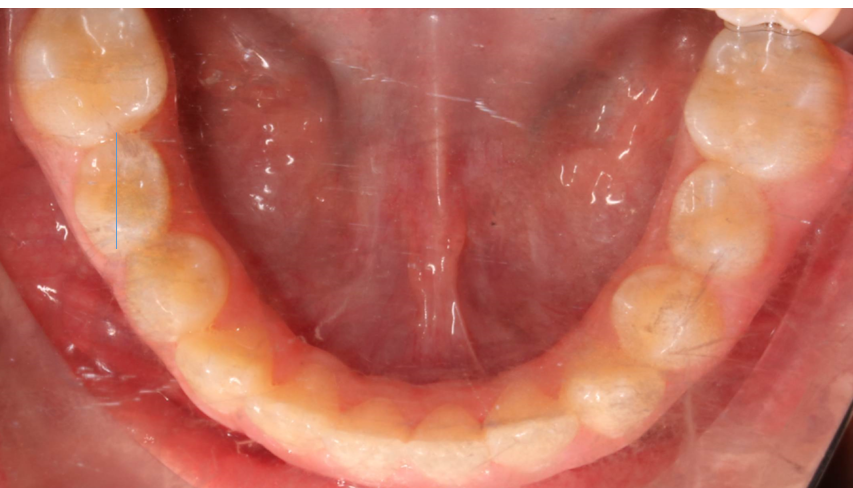

Llama la atención a primera vista la mordida abierta bilateral, especialmente pronunciada entre el cuadrante 1 y 4 debido a una interposición lingual en posición estática. Entre otros hallazgos fundamentales, observamos: un patrón dolicofacial severo (VERT: -2), una compresión de la arcada superior que cursa con un perfil y relación oclusal de clase III y la rotación del 35 y 45. Este caso se trató con un disyuntor, exodoncias de 44 y 34, brackets convencionales y educadores para rehabilitación de la lengua en un tiempo de 22 meses. Aunque estoy satisfecho con el resultado final, me hubiera gustado clavar la interscuspidación de premolares en el cuadrante I y IV, y mejorar la relación oclusal de cuadrante II y III. Sin embargo, lo bonito, es que hay a veces, en la ortodoncia real, que el paciente está satisfecho y quiere terminar antes de tiempo, o por el contrario, que el profesional intenta pero no consigue el resultado deseado. Y a mí más que compartir casos perfectos, me gusta mostrar mis errores, mi realidad.

ROTACIÓN DE PREMOLARES INFERIOREROTACIÓN DE 35 Y 45 DESROTAR CON PAR DE FUERZAS CON BOTONES